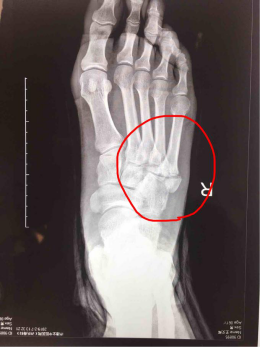

他院受診し、第5中足骨骨折と診断。 1ヶ月半以上経過するが、骨折部がズレ、骨癒合が望めない状態。 第5中足骨骨折の治療 画像検査(レントゲン) 赤く囲んだ部分が骨折している部分です。 画像検査(mri) 赤く囲んだ部分が骨折しているところです。中足骨(足の甲)は、疲労骨折を起こしやすい部位です。 スポンサーリンク 完治までの治療期間 治療法は主に経過観察となりますが、完治までの治療期間は、6週間~10週間はかかるとされています。 痛みがある場合、痛みは2週間~3週間もすれば 「第5中足骨骨折」治療と予防法 by 県境なき医師 七瀬 3月 22, 19 「足に違和感があるから整形外科に行ったら"下駄履き骨折"と言われた」「第5中足骨を骨折してしまったが、競技に復帰できるか不安」と思っている人もいることでしょう。

症例紹介 第5中足骨骨折に対しての治療 上田整形外科内科